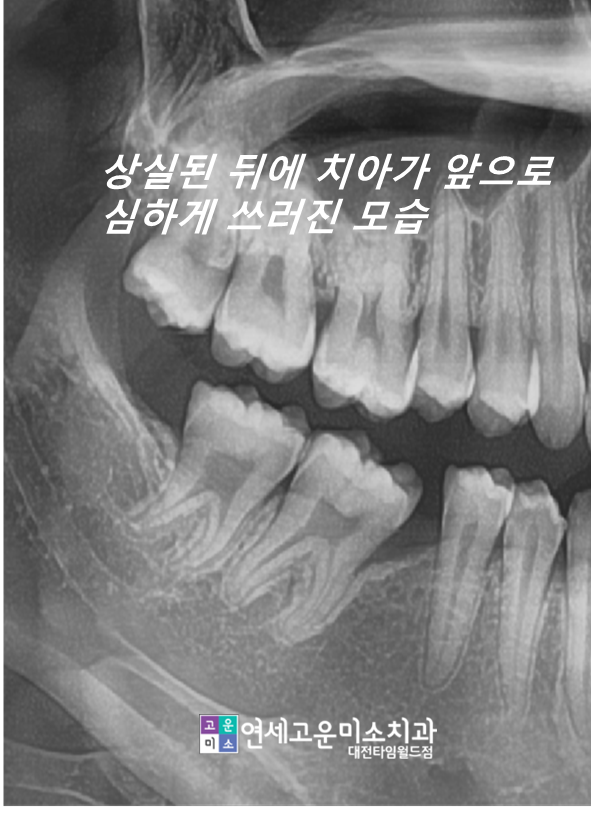

부분교정 케이스) 임플란트를 하고 싶은데 공간이 없어요

치아가 빠지고 나서 오래 방치되면

옆에 치아들이 그 공간으로 쓰러지게 됩니다.

공간이 너무 많이 없어지면

쓰러진 치아를 신경치료하고 씌운 다음에

임플란트를 심게 되는데요. 그렇게 되면

건강한 치아를 깎아야 되고

임플란트를 하더라도 음식물도 많이 끼게 됩니다.

위에 환자분도 공간이 너무 많이 소실되어

큰 어금니를 심을 수 없을 뿐만 아니라

작은 어금니 공간도 되지 않는 상태입니다.